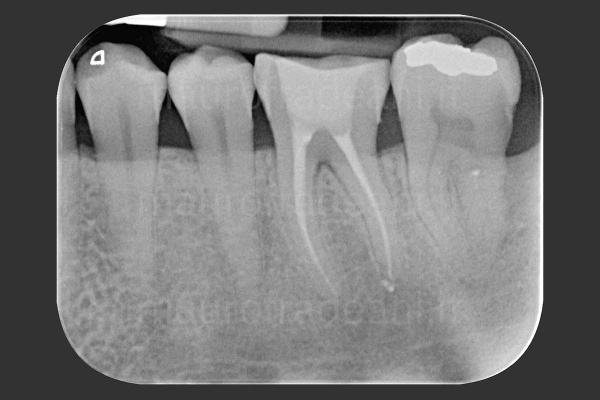

In tutti questi casi il trattamento endodontico (detto anche terapia canalare o devitalizzazione) è volto a salvare il dente ed evitarne l’estrazione.